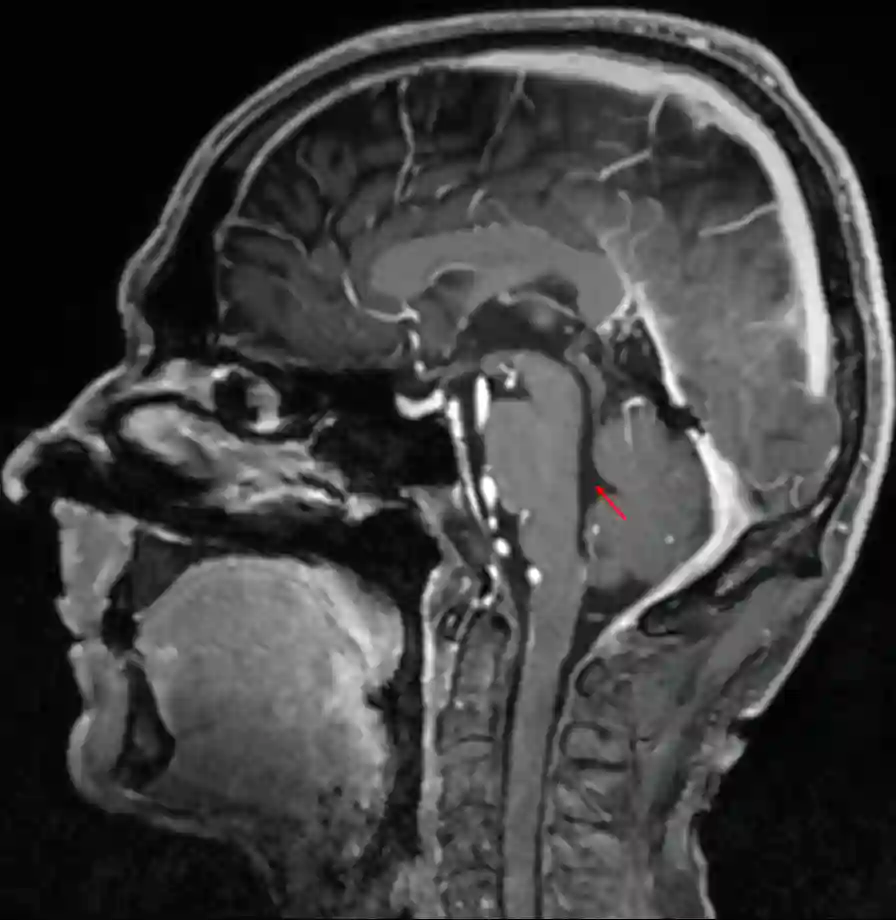

Der vierte Ventrikel ist Teil des Ventrikelsystems und befindet sich im Rhombencephalon.

Der vierte Ventrikel erhält über den Aquaeductus mesencephali Liquorzufluss aus dem dritten Ventrikel und steht so mit diesem in Verbindung. Der Boden des vierten Ventrikels bildet die Fossa rhomboidea. Nach beiden Seiten verläuft ein langer Recessus lateralis, an dessen Ende sich jeweils die Apertura lateralis (Foramen Luschkae) befindet und mit dem äußeren Liquorraum in Verbindung steht. Den aus der Apertura lateralis in den Subarachnoidalraum heraustretenden Plexus choroideus bezeichnet man als Bochdalek Blumenkörbchen. Des Weiteren findet sich ein Plexus choroideus am Dach des vierten Ventrikels am Velum medullare inferius. Median liegt die Apertura mediana (Foramen Magendi), welche ebenso mit dem äußeren Liquorraum in Verbindung steht. Der vierte Ventrikel setzt sich als Canalis centralis nach kaudal ins Rückenmark fort, welcher stellenweise obliteriert sein kann.

Im vierten Ventrikel können verschiedene Tumore lokalisiert sein. Medulloblastome gehen typischerweise vom Dach des vierten Ventrikels aus, wohingegen Ependymome häufig vom Boden des vierten Ventrikels ausgehen.

Eine Verlegung des Liquorabfluß im vierten Ventrikels kann zu einem Hydrocephalus führen.

Abbildung

Bildgebung